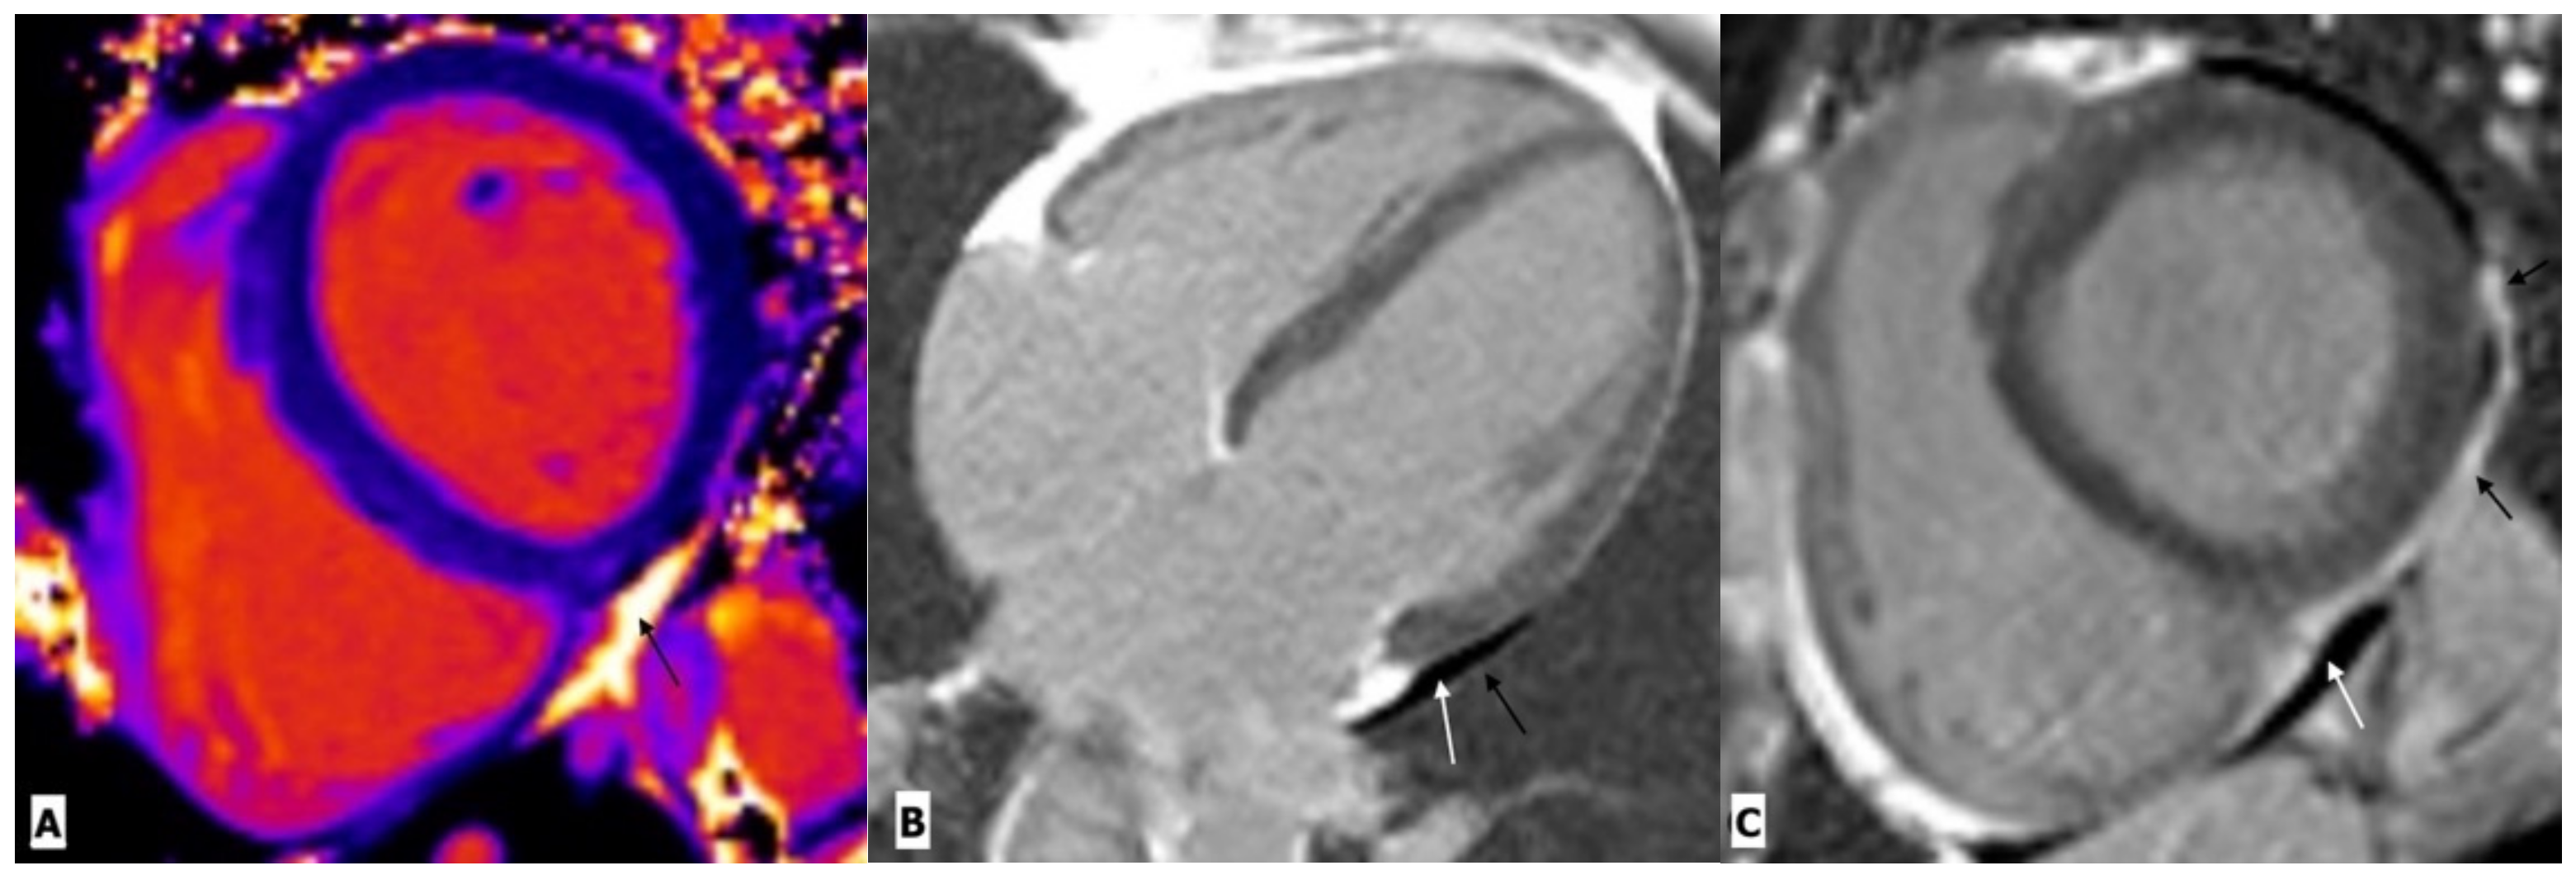

| Pericardial diseases | Himelman, R.B. et al. | Prospective observational study | 70 HIV infected patients | TTE | Pericardial effusion seen in 10% patients. |

| Akhras, F. et al. | Prospective observational study | 124 patients (101 with AIDS and 23 without opportunistic infection) | TTE | Pericardial effusion was more common in patients with AIDS (44%) as compared to HIV infected patients without opportunistic infections (9%). | |

| Ca rdiomyopathy | Sliwa, K. et al. | Prospective, registry study | 518 HIV infected patients | CMR | The most common primary diagnosis attributable to HIV/AIDS was HIV-related cardiomyopathy (38%), followed by pericarditis/pericardial effusion (25%), HIV-related pulmonary hypertension (8.1%), and coronary artery diseases (2.4%). |